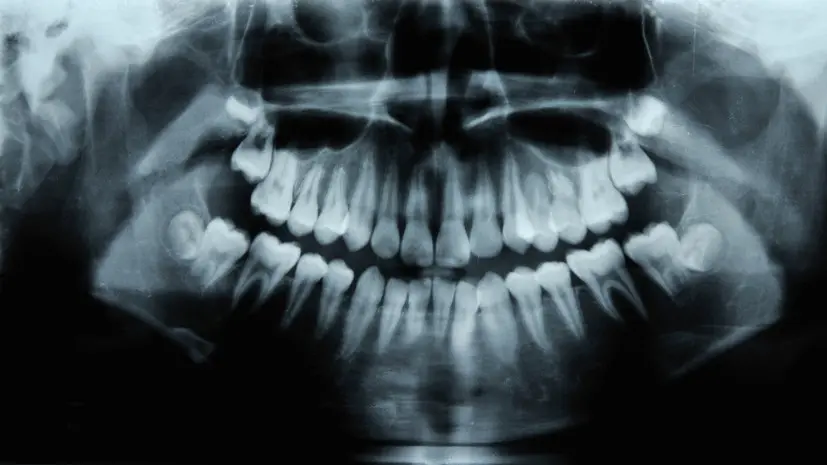

Специалист подчеркнула необходимость регулярных стоматологических осмотров каждые полгода для своевременного выявления и предотвращения проблем.